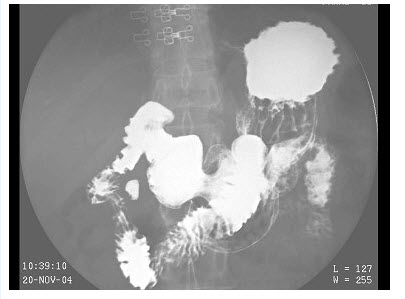

女,48岁,常感中上腹不适,无返酸、嗳气及黑便史,结合图像,最可能的诊断为()

A、正常肠圈

B、十二指肠炎

C、球部溃疡

D、降段憩室

E、水平段憩室

D